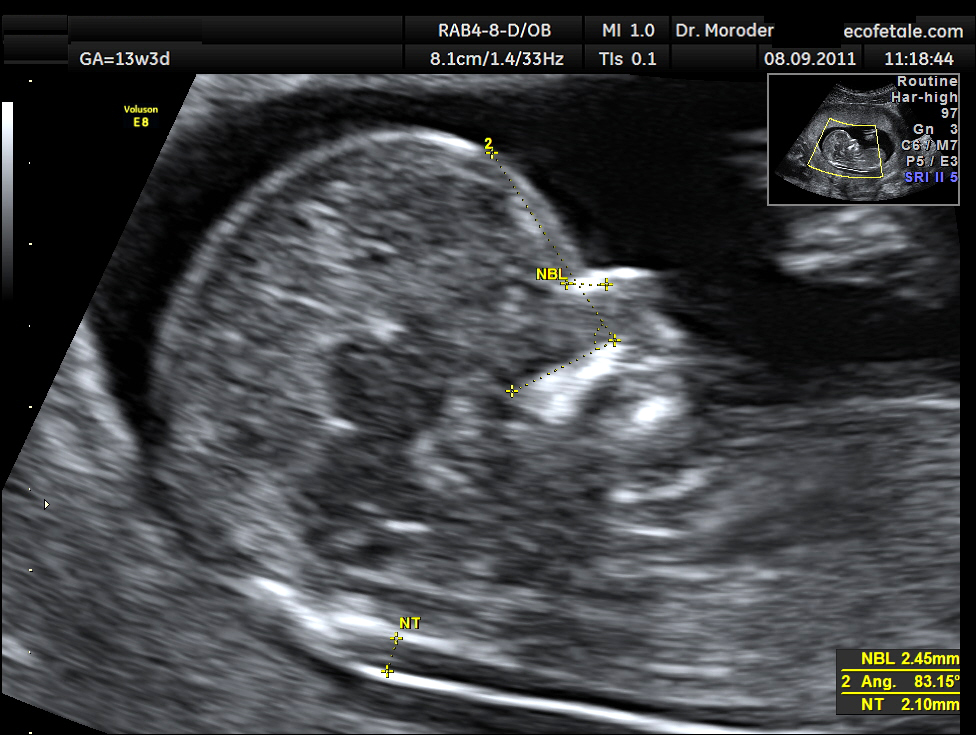

La translucenza nucale, entro un certo limite temporale, è in grado di identificare alcune patologie che possono affliggere il feto. In particolare, l’esame viene impiegato per sottolineare la presenza di Trisomia 18 e di Sindrome di Down, ma può portare alla luce anche altre sindromi, cardiopatie e cromosomopatie. Come avviene l’indagine? Normalmente, tramite un’ecografia effettuata per via sovrapubica. Essa può rendersi impraticabile in alcuni casi particolari, come la condizione di utero retroverso o anche nei casi di scarsa ecogenicità. In questo casi risulterà indispensabile un’ecografia transvaginale. Il momento ideale per effettuare una translucenza nucale corrisponde alla dodicesima settimana di gestazione e, per estensione, al periodo compreso tra le undici e le quattordici settimane. Tuttavia, spesso i feti affetti dalle anomalie elencate posso essere individuati già in epoca precoce, a partire dall’ottava o nona settimana.

L’esame in questione consiste nella misurazione dello spessore della plica nucale del feto. In genere, tale parametro aumenta (quando si verificano anomalie cromosomiche ma anche patologie cardiache) in quel determinato stadio di gravidanza. L’aumento è transitorio e regredisce nel giro di alcune settimane. Per tale motivo, la translucenza nucale si rivela particolarmente utile anche per coloro che in seguito effettueranno villocentesi o amniocentesi. Nei feti sani, il valore della TN dovrebbe essere compreso tra 1.1 e 1.4 millimetri. Il valore massimo considerato da esperti e studiosi coincide con i 2.5 millimetri, oltre il quale si sconfina nel campo della patologia.